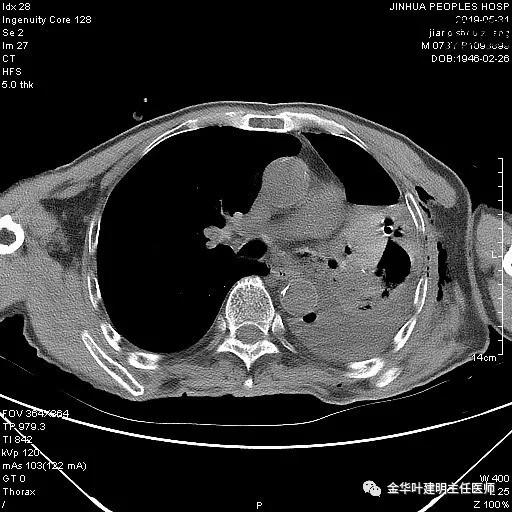

考虑左侧大量胸腔积液,遂进一步胸部CT检查:

以上是肺窗表现,下面为纵隔窗影像:

因为引流出的胸液为血性,但感觉不是特别鲜,查血色素9.5 g/L,术前是12.7g/L。当时考虑胸腔内出血可能,较为纠结的是是否需要进胸探查。但鉴于血压正常、心率不快,一般情况良好,不似胸内大出血休克的表现,所以仍想继续观察保守治疗。